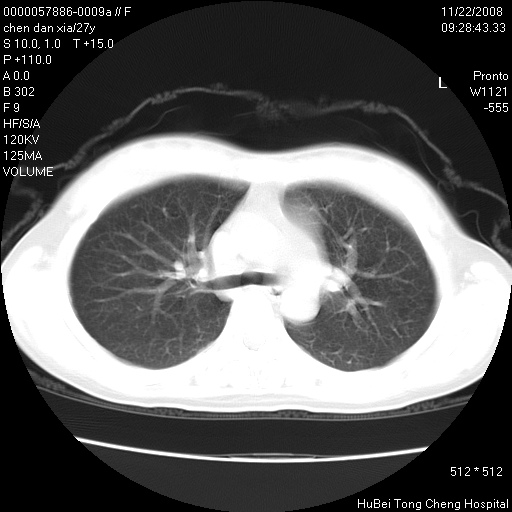

标题: CT16752:F,27Y。发热咳嗽20余天,伴盗汗。 [打印本页]

标题: CT16752:F,27Y。发热咳嗽20余天,伴盗汗。

考虑双肺粟粒性肺tb,右侧胸膜增厚.

气管前腔静脉后淋巴结肿大 右肺门纹理模糊

淋巴结核?

右下肺见片絮状影,两肺野内分布不均的小结节影,结核并肺内播散可能性大,建议结合实验室检查 .

右下肺纹理模糊;纵隔可见肿大淋巴节;右心缘旁结节,边缘光滑,纵隔窗病变范围较肺窗明显小,首先考虑右下肺结核,不排外淋巴瘤

双肺纹影普多,部分呈网状,支炎或淋巴管炎?

纵隔内淋结肿

局部胸膜增厚

下肺结节,结节内钙化,肺门纵隔淋巴肿大 结核可能性大

似有粟米状结节。考虑粟粒型肺结核?

1)考虑两肺感染性病变。2)纵隔淋巴结肿大。